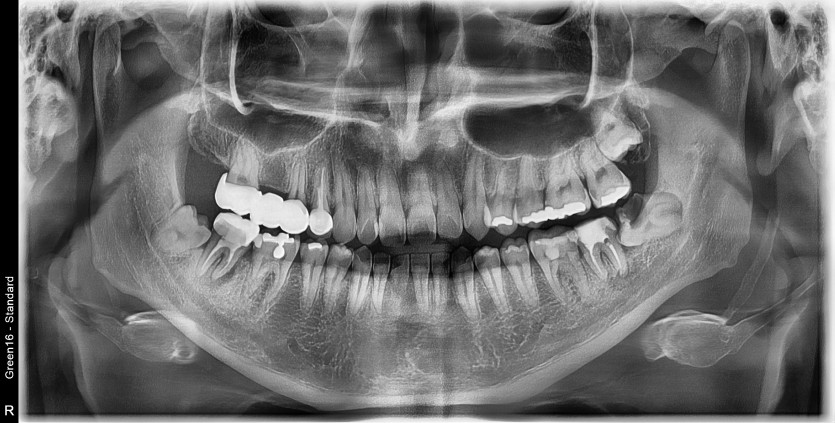

#38 사랑니 발치 (#37 발치 포함)

구강 외과 전문의가 당일 발치했습니다.